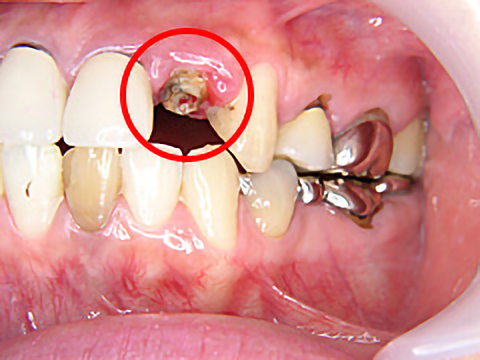

歯科治療が怖くて長きにわたりお口を放置されていましたが、一大決心の後、当院にて治療を受けられました。

右上4本、左上も3本、抜歯即時埋入を含めてインプラント治療を受け、噛み合わせを取り戻すことができました。また、下顎の前歯も大きくすり減っていたため、オールセラミックスで治療しました。